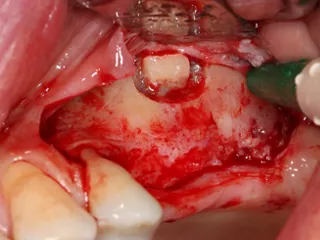

5. A full-thickness flap was elevated and a releasing incision made mesial to 24. Care must be taken at this stage not to damage the periosteum.

6. A lateral sinus lift was performed by creating a 7 × 5 mm window using a round tungsten carbide bur followed by a diamond bur.

7. The bony window was removed and placed in saline solution so that it could be placed back in position after grafting. The Schneiderian membrane was released without perforation.